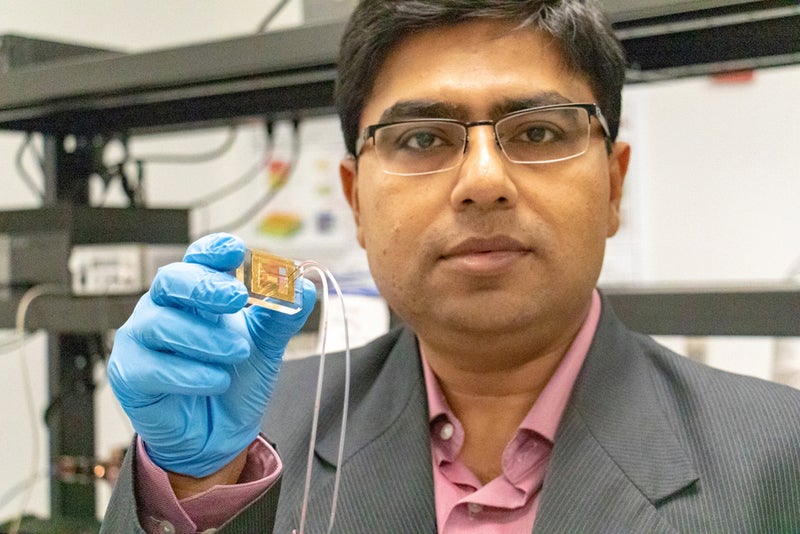

A new test that measures dopamine levels in biological fluids could help with the detection of depression, Parkinson's disease, and other disordered marked by abnormal dopamine levels.

In Parkinson's, Tiny New Sensor Measures Dopamine in Nerve Cells

New dopamine sensor could help detect brain disorders rapidly